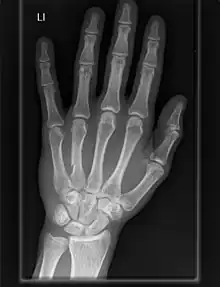

Las articulaciones carpometacarpianas (CMC) son cinco articulaciones de la muñeca que articulan la fila distal de los huesos del carpo y las bases proximales de los cinco huesos metacarpianos.

Dedos

- El segundo metacarpiano se articula principalmente con el trapezoide y secundariamente con el trapecio y el capitado.

- El tercer metacarpiano se articula principalmente con el capitado,

- El cuarto metacarpiano se articula con el capitado y el hueso ganchoso.

- El quinto metacarpiano se articula con el hueso ganchoso.[7]

Entre ellos, los cuatro metacarpianos cubitales también se articulan con sus vecinos en las articulaciones intermetacarpianas.[7]

Las articulaciones carpometacarpianas de los dedos segundo a quinto son artrodiales. Los movimientos permitidos en las articulaciones carpometacarpianas del segundo al quinto son más fácilmente observables en las cabezas (distales) de los huesos metacarpianos. El rango de movimientos en estas articulaciones disminuye desde la quinta a la segunda CMC.[8]

Las articulaciones segunda a quinta son articulaciones sinoviales elipsoidales con un grado de libertad nominal (flexión/extensión). Sin embargo, las articulaciones segunda y tercera son esencialmente inmóviles y se puede considerar que tienen cero grados de libertad en la práctica. Estas dos CMC proporcionan a las otras tres CMC un eje fijo y estable. Mientras que la movilidad de la cuarta articulación CMC es, por tanto, perceptible, la primera articulación es una articulación en silla de montar con dos grados de libertad que, además de la flexión/extensión, también permiten la abducción/aducción y una cantidad limitada de oposición. El conjunto de los movimientos de la cuarta y quinta CMC facilita que sus dedos se opongan al pulgar.[8]